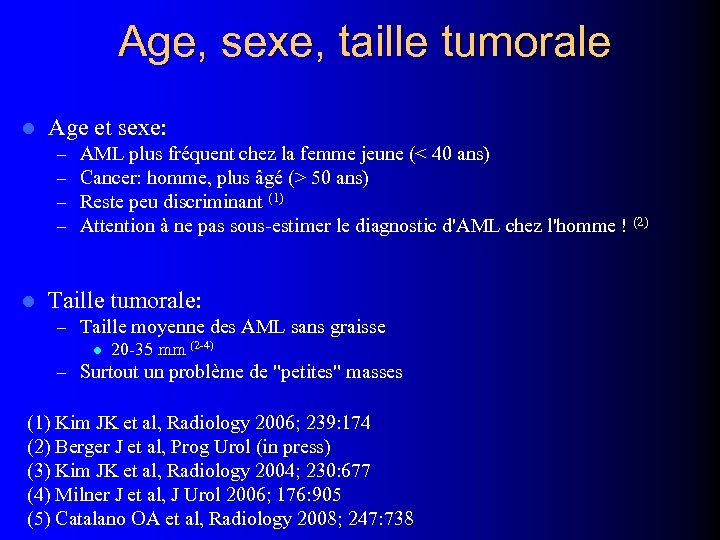

Age, sexe, taille tumorale l Age et sexe: – – l AML plus fréquent chez la femme jeune (< 40 ans) Cancer: homme, plus âgé (> 50 ans) Reste peu discriminant (1) Attention à ne pas sous-estimer le diagnostic d'AML chez l'homme ! (2) Taille tumorale: – Taille moyenne des AML sans graisse l 20 -35 mm (2 -4) – Surtout un problème de "petites" masses (1) Kim JK et al, Radiology 2006; 239: 174 (2) Berger J et al, Prog Urol (in press) (3) Kim JK et al, Radiology 2004; 230: 677 (4) Milner J et al, J Urol 2006; 176: 905 (5) Catalano OA et al, Radiology 2008; 247: 738

Age, sexe, taille tumorale l Age et sexe: – – l AML plus fréquent chez la femme jeune (< 40 ans) Cancer: homme, plus âgé (> 50 ans) Reste peu discriminant (1) Attention à ne pas sous-estimer le diagnostic d'AML chez l'homme ! (2) Taille tumorale: – Taille moyenne des AML sans graisse l 20 -35 mm (2 -4) – Surtout un problème de "petites" masses (1) Kim JK et al, Radiology 2006; 239: 174 (2) Berger J et al, Prog Urol (in press) (3) Kim JK et al, Radiology 2004; 230: 677 (4) Milner J et al, J Urol 2006; 176: 905 (5) Catalano OA et al, Radiology 2008; 247: 738